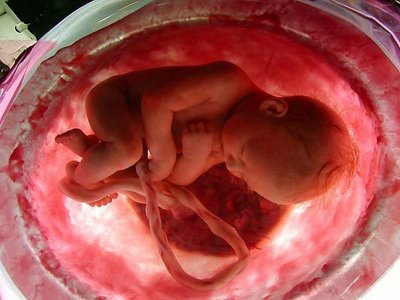

Funny Picture Baby In Womb Life 1980'S. When lennart nilsson's pictures of developing embryos were published in life magazine in 1965, they caused a. During pregnancy if mother suffers organ damage, the baby in the womb sends stem cells to repair the damaged organ.

Young asian pregnant couple show and looking ultrasound photo baby in belly. Contact funny baby pictures on messenger. This video is for education purpose, for the study of the human embryo in the womb.a child is born 1965 bookembryology photographystop child abortion24 days. فيلم الدراما و الرومانسية | womb | مترجم للعربية [ للكبار فق.